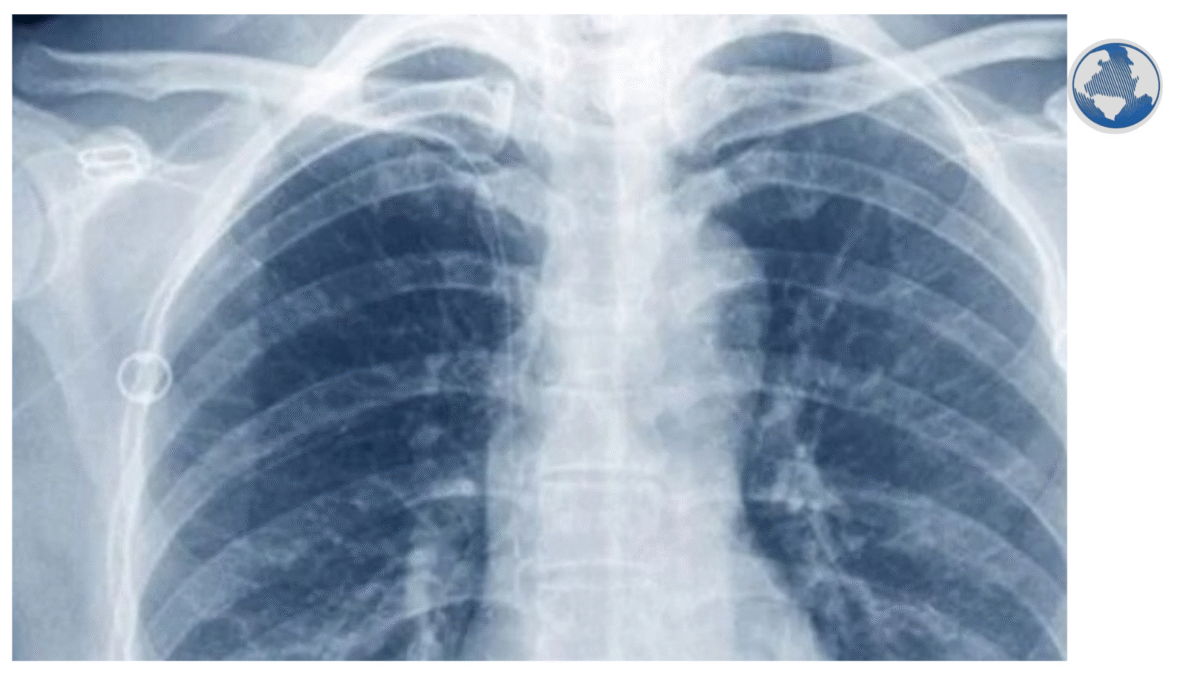

33-ամյա տղամարդը հոսպիտալացվել է 2023 թվականին և միացված է եղել արհեստական շնչառության սարքին, գրում է Planet Today-ը: Խնդրի պատճառը գրիպից հետո առաջացած բարդությունն էր՝ թոքային անբավարարության զարգացումը, որը հանգեցրել է նեկրոզային թոքաբորբի և սեպսիսի (արյան վարակման): Հակաբիոտիկները չեն օգնել, քանի որ բուժառուի մոտ լիակատար (resistance) դիմադրողականություն է զարգացել,- մեկնաբանում է Հյուսիսարևմտյան համալսարանի գիտաշխատող, նոր տեխնոլոգիայի հեղինակ Անկիտ Բհարատը:

Նման պահերին բժիշկները հայտնվում են երկընտրանքի առաջ. երկու թոքերի լրիվ հեռացումը կարող է դադարեցնել վարակը, սակայն առանց թոքերի խաթարվում է գազափոխանակությունը և արյան շրջանառությունը, ինչը կարող է հանգեցնել սրտի կանգի և մահվան:

Բհարատը մշակել է արհեստական թոքային համակարգ, որը կարող է ամբողջությամբ փոխարինել օրգանը, թթվածին մատակարարել արյանը և աջակցել արյան շրջանառությանը,-գրում է համալսարանի կայքը: